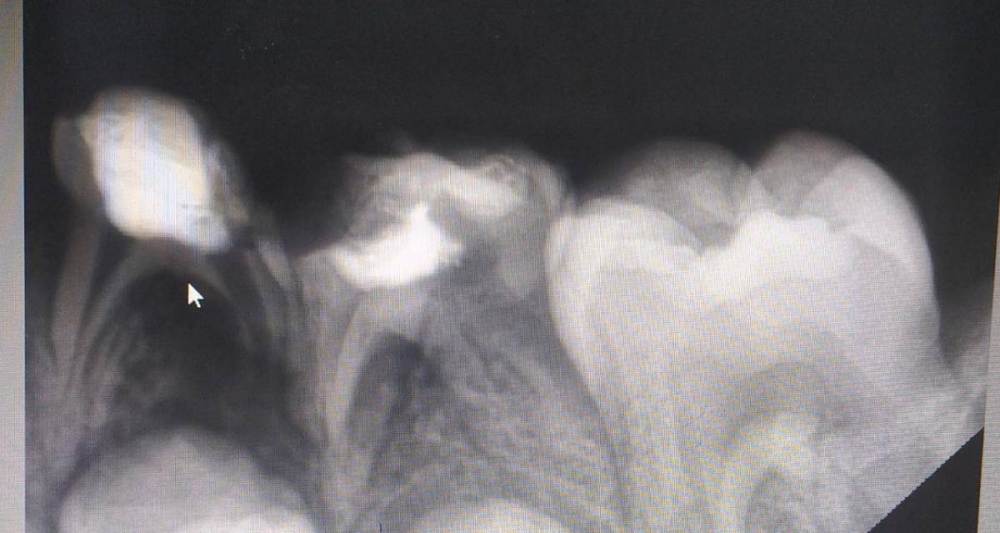

Anna17 Опубликовано 19 июля, 2022 Поделиться Опубликовано 19 июля, 2022 Здравствуйте! Ребенку 6 лет. 4-ку удалили, показана ли к удалению 5-ка или можно полечить? Врач переживает за постоянный зуб. Ссылка на комментарий